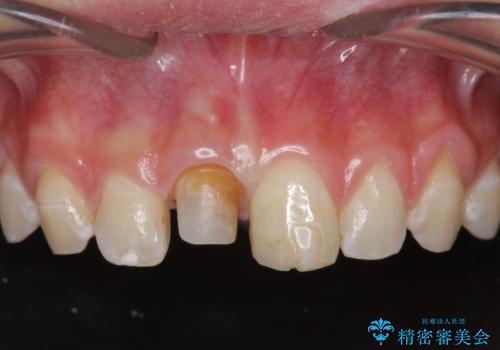

前歯をきれいにしたい ジルコニアクラウンによる審美治療

- 前歯の見た目の改善を求めて来院されました。

ジルコニアクラウンによる審美性の改善を計画します。

失活歯のため捻転を改善し、根管治療は特に希望されなかったのでそのままとしました。

今回失活歯であったため捻転を取り反対側の前歯に揃えて補綴を行うことができました。